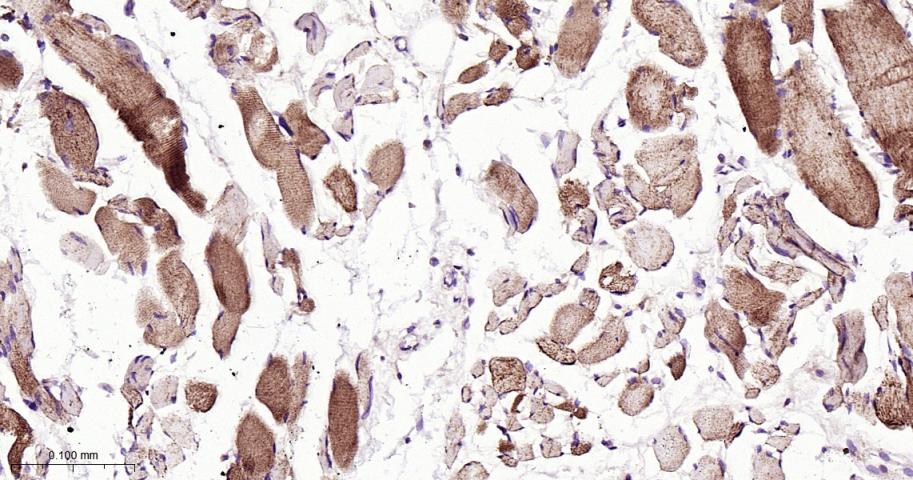

Paraformaldehyde-fixed, paraffin embedded Human Skeletal muscle ; Antigen retrieval by boiling in sodium citrate buffer (pH6.0) for 15 min; Antibody incubation with ATG4C Monoclonal Antibody, Unconjugated(bsm-61516R) at 1:200 overnight at 4°C, followed by conjugation to the bs-0295G-HRP and DAB (C-0010) staining.